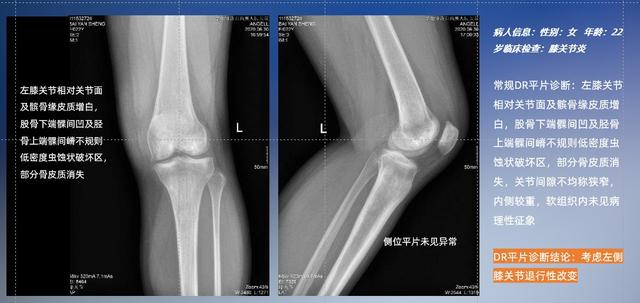

普通平片扫描与WR-3D扫描前后诊断结果对比

在负重位状态下,数字化X线三维扫描与重建,能够更好的呈现受检者关节受力改变的状态。广东会科技创新的WR-3D动态三维影像重建系统,通过数字化X线摄影完成三维扫描并重建三维影像信息,包括断层图像重建、MPR多平面重建、MIP重建以及VR体绘制。其扫描时间短,剂量相较于CT设备大幅缩减,同时成本更低,在临床诊断以及医疗方案制定中具有极大的价值意义。而相较于普通平片下的负重位扫描,负重位动态三维影像重建技术能够避免二维状态下的组织结构重叠、密度分辨率不足、组织解剖结构难以分辨等问题。WR-3D支持多角度的三维观察,能全面的呈现被检查部位在多个角度下的三维影像信息,极大的降低了二维负重位检查带来的漏诊率。